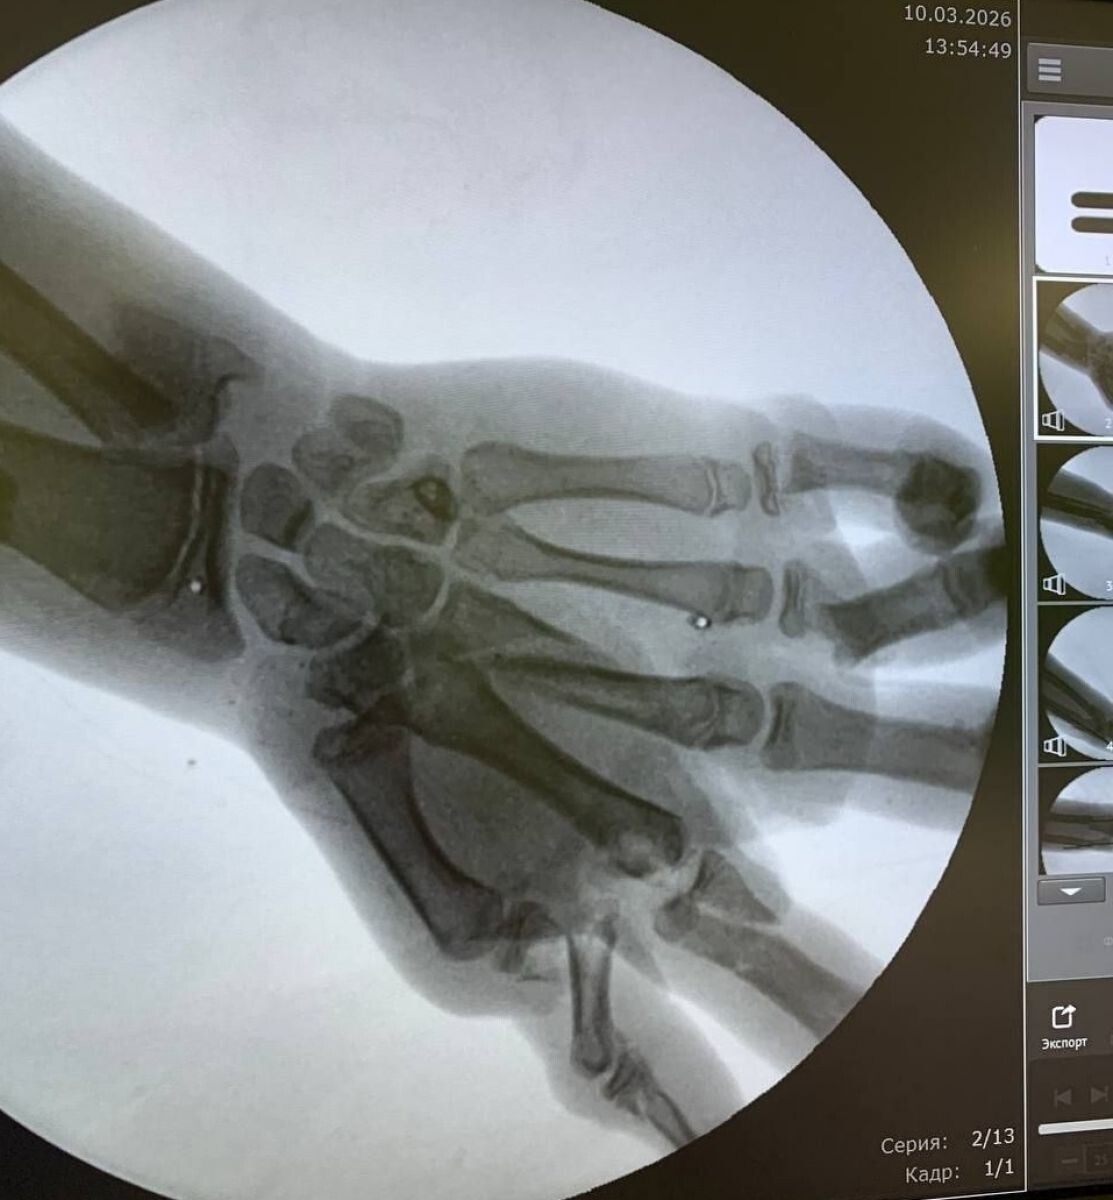

Врачи Калининграда спасли кисть подростку, пострадавшему от взрыва снаряда

С тяжелыми травмами мальчика доставили в больницу в шоковом состоянии. У него были перелом предплечья со смещением, раны на ноге и лбу, но самое опасное — множественные переломы и сильное кровотечение в левой кисти. Врачи опасались, что конечность могут не спасти.

Специалисты немедленно провели операцию, которая длилась полтора часа. Хирургам удалось остановить кровотечение, очистить раны от загрязнений и собрать костные обломки кисти. Главной задачей было восстановить кровоток в поврежденной руке.

Из-за особенностей взрывных травм сразу невозможно точно определить, какие ткани погибли, а какие можно спасти. Через несколько дней врачи провели вторую операцию, во время которой устранили дефекты тканей и костей с помощью пластики.